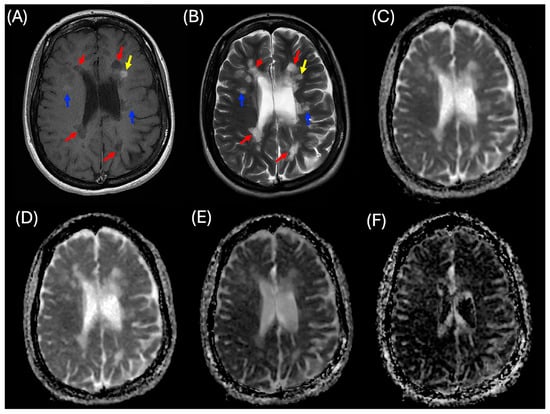

2.2. Lesion Analysis

2.3. MRI Imaging Protocols

2.4. MRI Processing